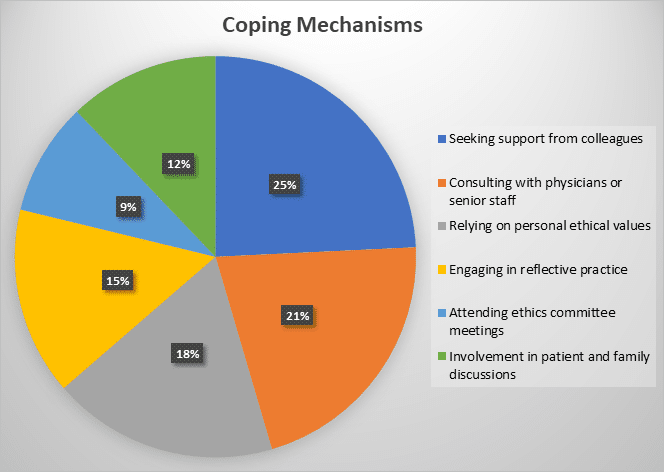

Nurses’ Experiences with Ethical Dilemmas in Critical Care Settings: A Mixed-Method Study at Saidu Teaching Hospital

Background: Critical care nurses (CCNs) routinely experience multiple ethical dilemmas that force them to test their ability to make decisions...Read More